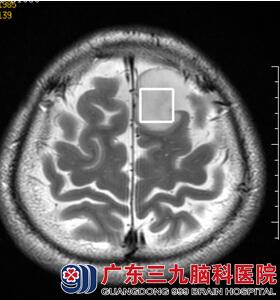

29岁的杨先生,因“发作性意识丧失伴四肢抽搐7天”到广东三九脑科医院就诊。入院前在当地医院检查头颅磁共振示:左侧额叶皮层区异常信号,考虑低级别胶质瘤。

入院后完善术前相关检查及术前准备,由林涛主任在全麻下行左侧额叶肿瘤切除术,手术顺利,术后杨先生的生命体征平稳,神志清楚,术后病理结果回报:星形细胞瘤,WHO II级,术后第十天予头部伤口拆线,伤口愈合良好。